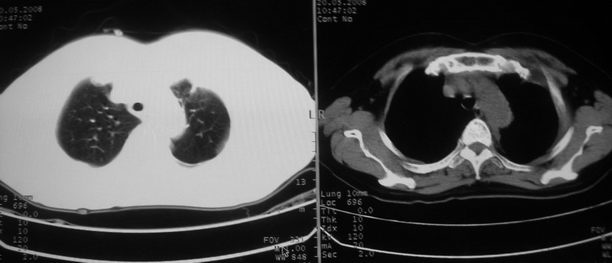

以下是引用w_jianhua在2008-5-22 12:59:00的发言:[br]1.左肺上叶肺癌并左侧胸腔积液可能性大。2不除外支气管内膜结核并包裹性胸腔积液,建议支气管镜检3.左肺下叶肺大泡,肺气肿